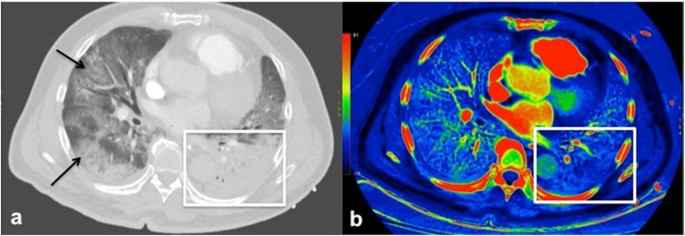

a Axial image from CT pulmonary angiogram showing dense consolidation in the left lung (white frame) and ground glass opacities in the right lung (black arrows). b Corresponding iodine image shows a perfusion defect within the left lung with a surrounding halo of increased perfusion (white frame). No pulmonary embolism was detected